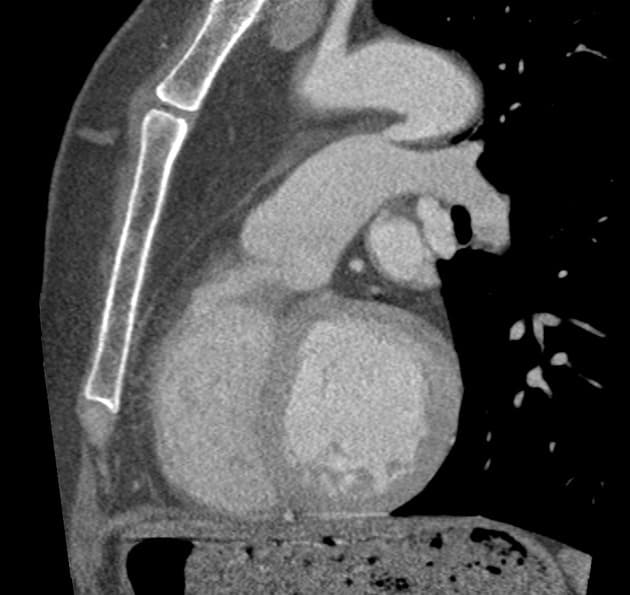

Sagittal thin C+ arterial phase

Không thấy tổn thương động mạch chủ do chấn thương hoặc máu tụ trung thất. Ghi nhận thấy ống động mạch còn thông (patent ductus arteriosus).

- Không tổn thương động mạch chủ do chấn thương. Ống động mạch còn thông có đường kính nhỏ, không có dấu hiệu tăng áp động mạch phổi hoặc phì đại thất phải (RV hypertrophy). Gợi ý hội chẩn với chuyên khoa Tim mạch (Cardiology review suggested).

Ống động mạch (ductus arteriosus) là một mạch máu nối động mạch chủ xuống gần đoạn đầu với phần trần của thân động mạch phổi gần nơi xuất phát của động mạch phổi trái. Bình thường, ống này tự đóng trong vòng 24–48 giờ sau sinh do tăng áp lực oxy và giảm nồng độ prostaglandin. Việc không đóng lại sẽ dẫn đến tình trạng ống động mạch còn thông (patent ductus arteriosus – PDA).

Trong bối cảnh chấn thương, việc phân biệt giữa PDA và tổn thương động mạch chủ do chấn thương là rất quan trọng. Trong trường hợp này, vị trí giải phẫu, không có bất thường thành mạch, cùng với việc không có máu tụ trung thất hoặc các tổn thương ngực đáng kể khác giúp khẳng định chẩn đoán PDA.

- "Phân biệt PDA với tổn thương động mạch chủ do chấn thương trên CT rất quan trọng: PDA không có bất thường thành mạch, không máu tụ và có vị trí giải phẫu đặc trưng."